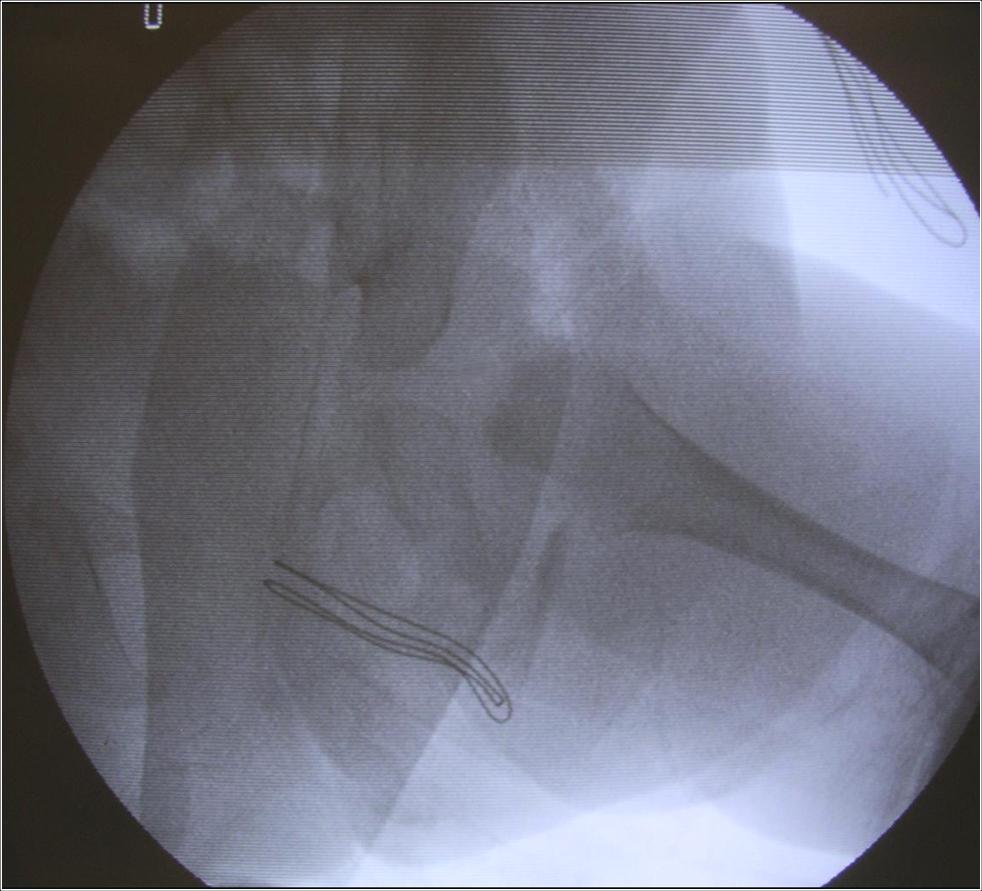

La centrazione viene ottenuta attraverso il confezionamento di gessi pelvi-podalici modellati in anestesia generale, preceduti o meno da una trazione progressiva dell’arto inferiore.

Quest’ultima, riservata soprattutto ai casi di Lussazione dell’Anca (LCA), è eseguita in ambiente ospedaliero sotto uno stretto controllo medico-infermieristico.

In rari casi, anche con il confezionamento di un gesso, la riduzione non è ottenuta, ad indicare la presenza di ingombri fisici che ne impediscono la riduzione. L’unico modo per ripristinare la congruenza articolare è rimuoverli con un intervento chirurgico mirato. A seguito l’immobilizzazione in gesso permette la formazione di una cicatrice resistente, mantenendo in sede i capi articolari.